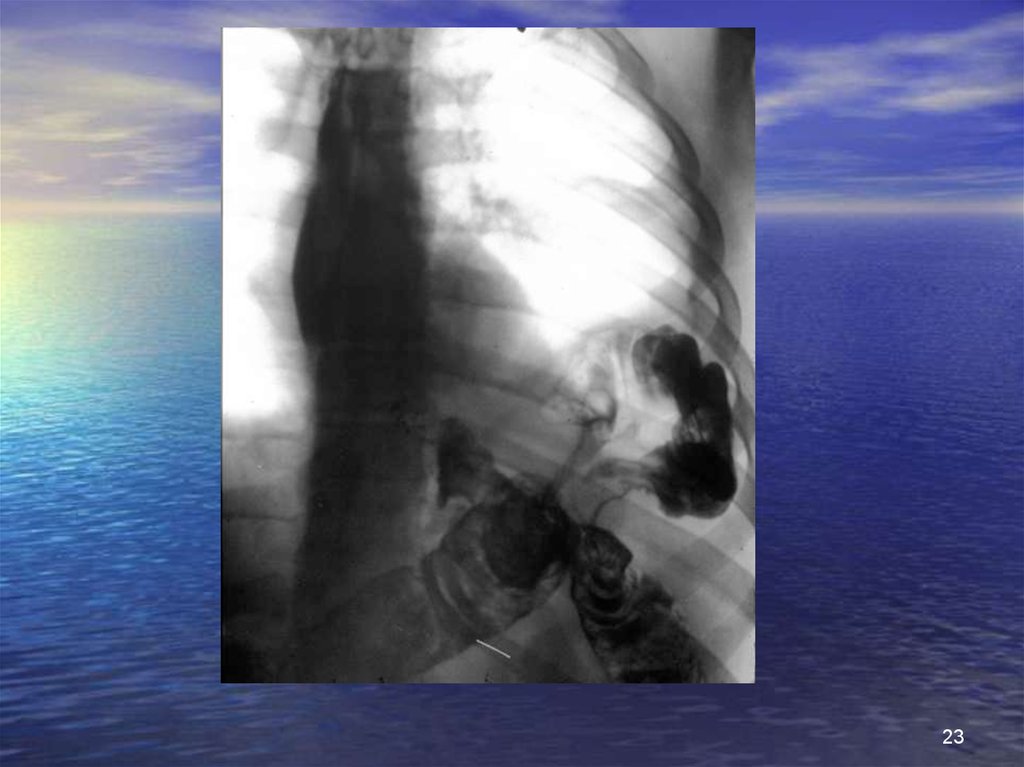

Разрыв диафрагмы (3)

рентгенологические исследования

• Очевидное повреждение диафрагмы

картина повышенной гидроаэрогенности внутри грудной клетки

грыжа с содержимым из полых органов

установка зонда;

ввести водорастворимый контраст;

картина затемненная: органы паренхимы

• Повреждения с трудной интерпретацией

поднят купол диафрагмы плохо визуализируется;

ателектазы;

гемо- или пневмоторакс;

затемнения базы легких